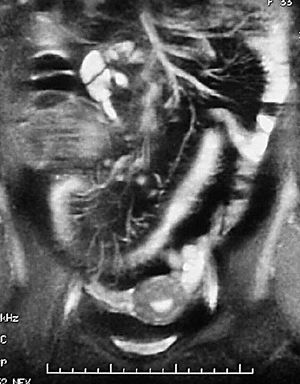

Para los pacientes con EC el riesgo de padecer una fístula durante su vida se sitúa entre el 20 y el 40%. En el caso de las fístulas perianales el riesgo es acumulativo y aumenta con el paso de los años: del 21% a los 10 años, al 26% después de los 20 años de enfermedad18. En el diagnóstico por imagen de las fístulas anorrectales la fistulografía está siendo reemplazada por la RM, que ha demostrado gran precisión a la hora de determinar y diferenciar los trayectos fistulosos y abscesos8,19,20. Las ventajas de la RM frente a la TC son la mayor resolución tisular en el estudio de partes blandas de la región pélvica y la mayor resolución espacial.

La RM es una técnica que surge con un gran potencial en el estudio del intestino delgado, fundamentalmente en pacientes de este tipo, puesto que no supone radiación ionizante. Se trata de una patología inflamatoria crónica, de carácter recurrente, en pacientes jóvenes con una gran esperanza de vida, en los que hay que minimizar la exposición a radiaciones ionizantes, y probablemente en un futuro no lejano la RM va a ejercer un importante papel en el estudio de estos pacientes. En concreto la RM ha demostrado gran precisión en el estudio de las fístulas anorrectales, a la hora de determinar y diferenciar los trayectos fistulosos7,8.